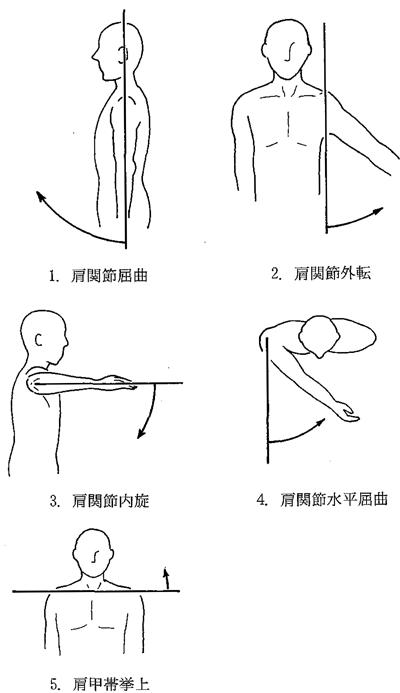

62

第34回 午前

|

作業療法士専門問題

最重要

ブルンストローム法における上肢回復段階の屈筋共同運動の組合せで正しいのはどれか。

1

肩甲帯挙上と後方突出-肩関節内転と外旋-肘関節屈曲

2

肩甲帯前方突出-肩関節外転と内旋-肘関節屈曲

3

肩甲帯挙上と後方突出-肩関節外転と外旋-肘関節屈曲

4

肩甲帯前方突出-肩関節内転と内旋-肘関節伸展

5

肩甲帯挙上と後方突出-肩関節内転と外旋-肘関節伸展